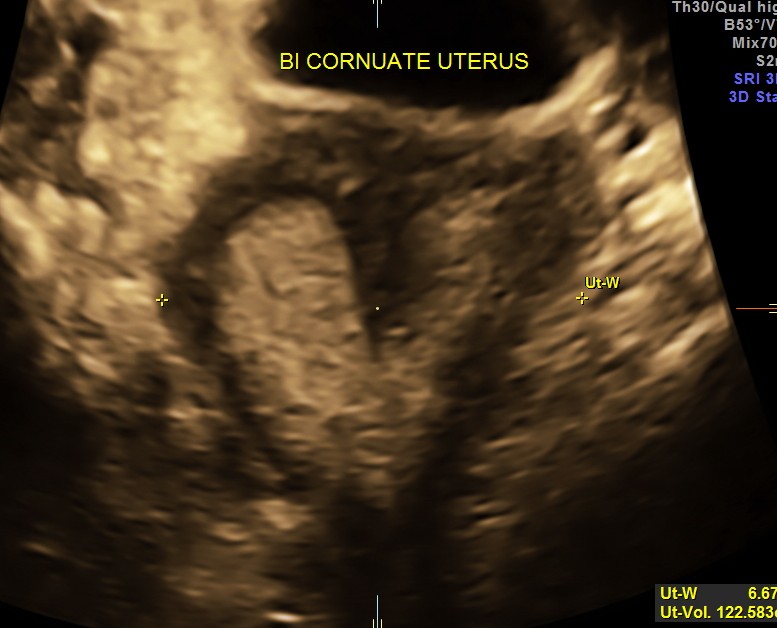

Pelvic scan revealed bi cornuate uterus ( incidental ) . She dad 3 children and never had any gynecological complaints

The diagnosis offered was Cholelithiasis , Choledochal cysts Type IV A and incidental bi cornuate uterus.